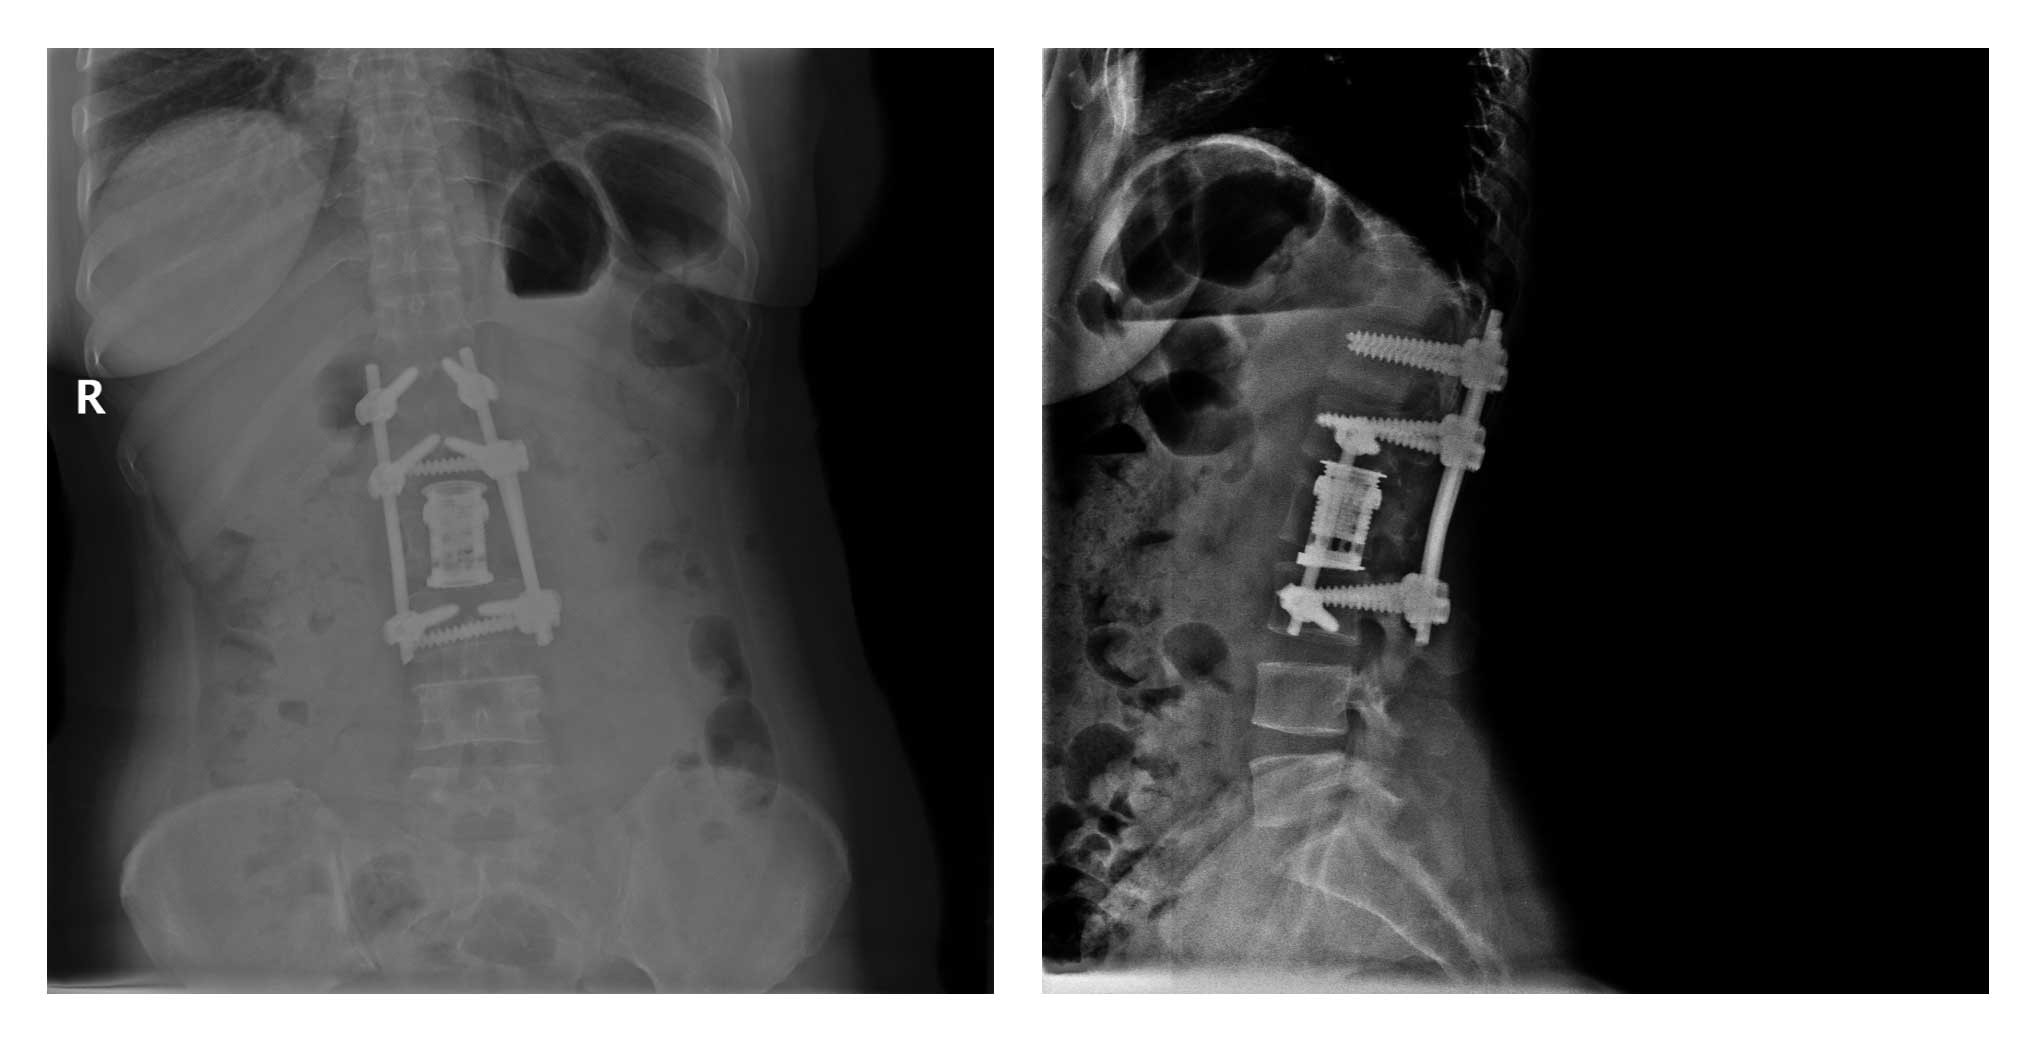

Ameliyat Esnası: Posteriordan laminektomi yapılması ve köklerin serbestleştirilmesi sonrası anteriordan korpektominin tamamlanması, asansör cage yerleştirilmesi ve enstrümentasyon uygulanması görülmekte.